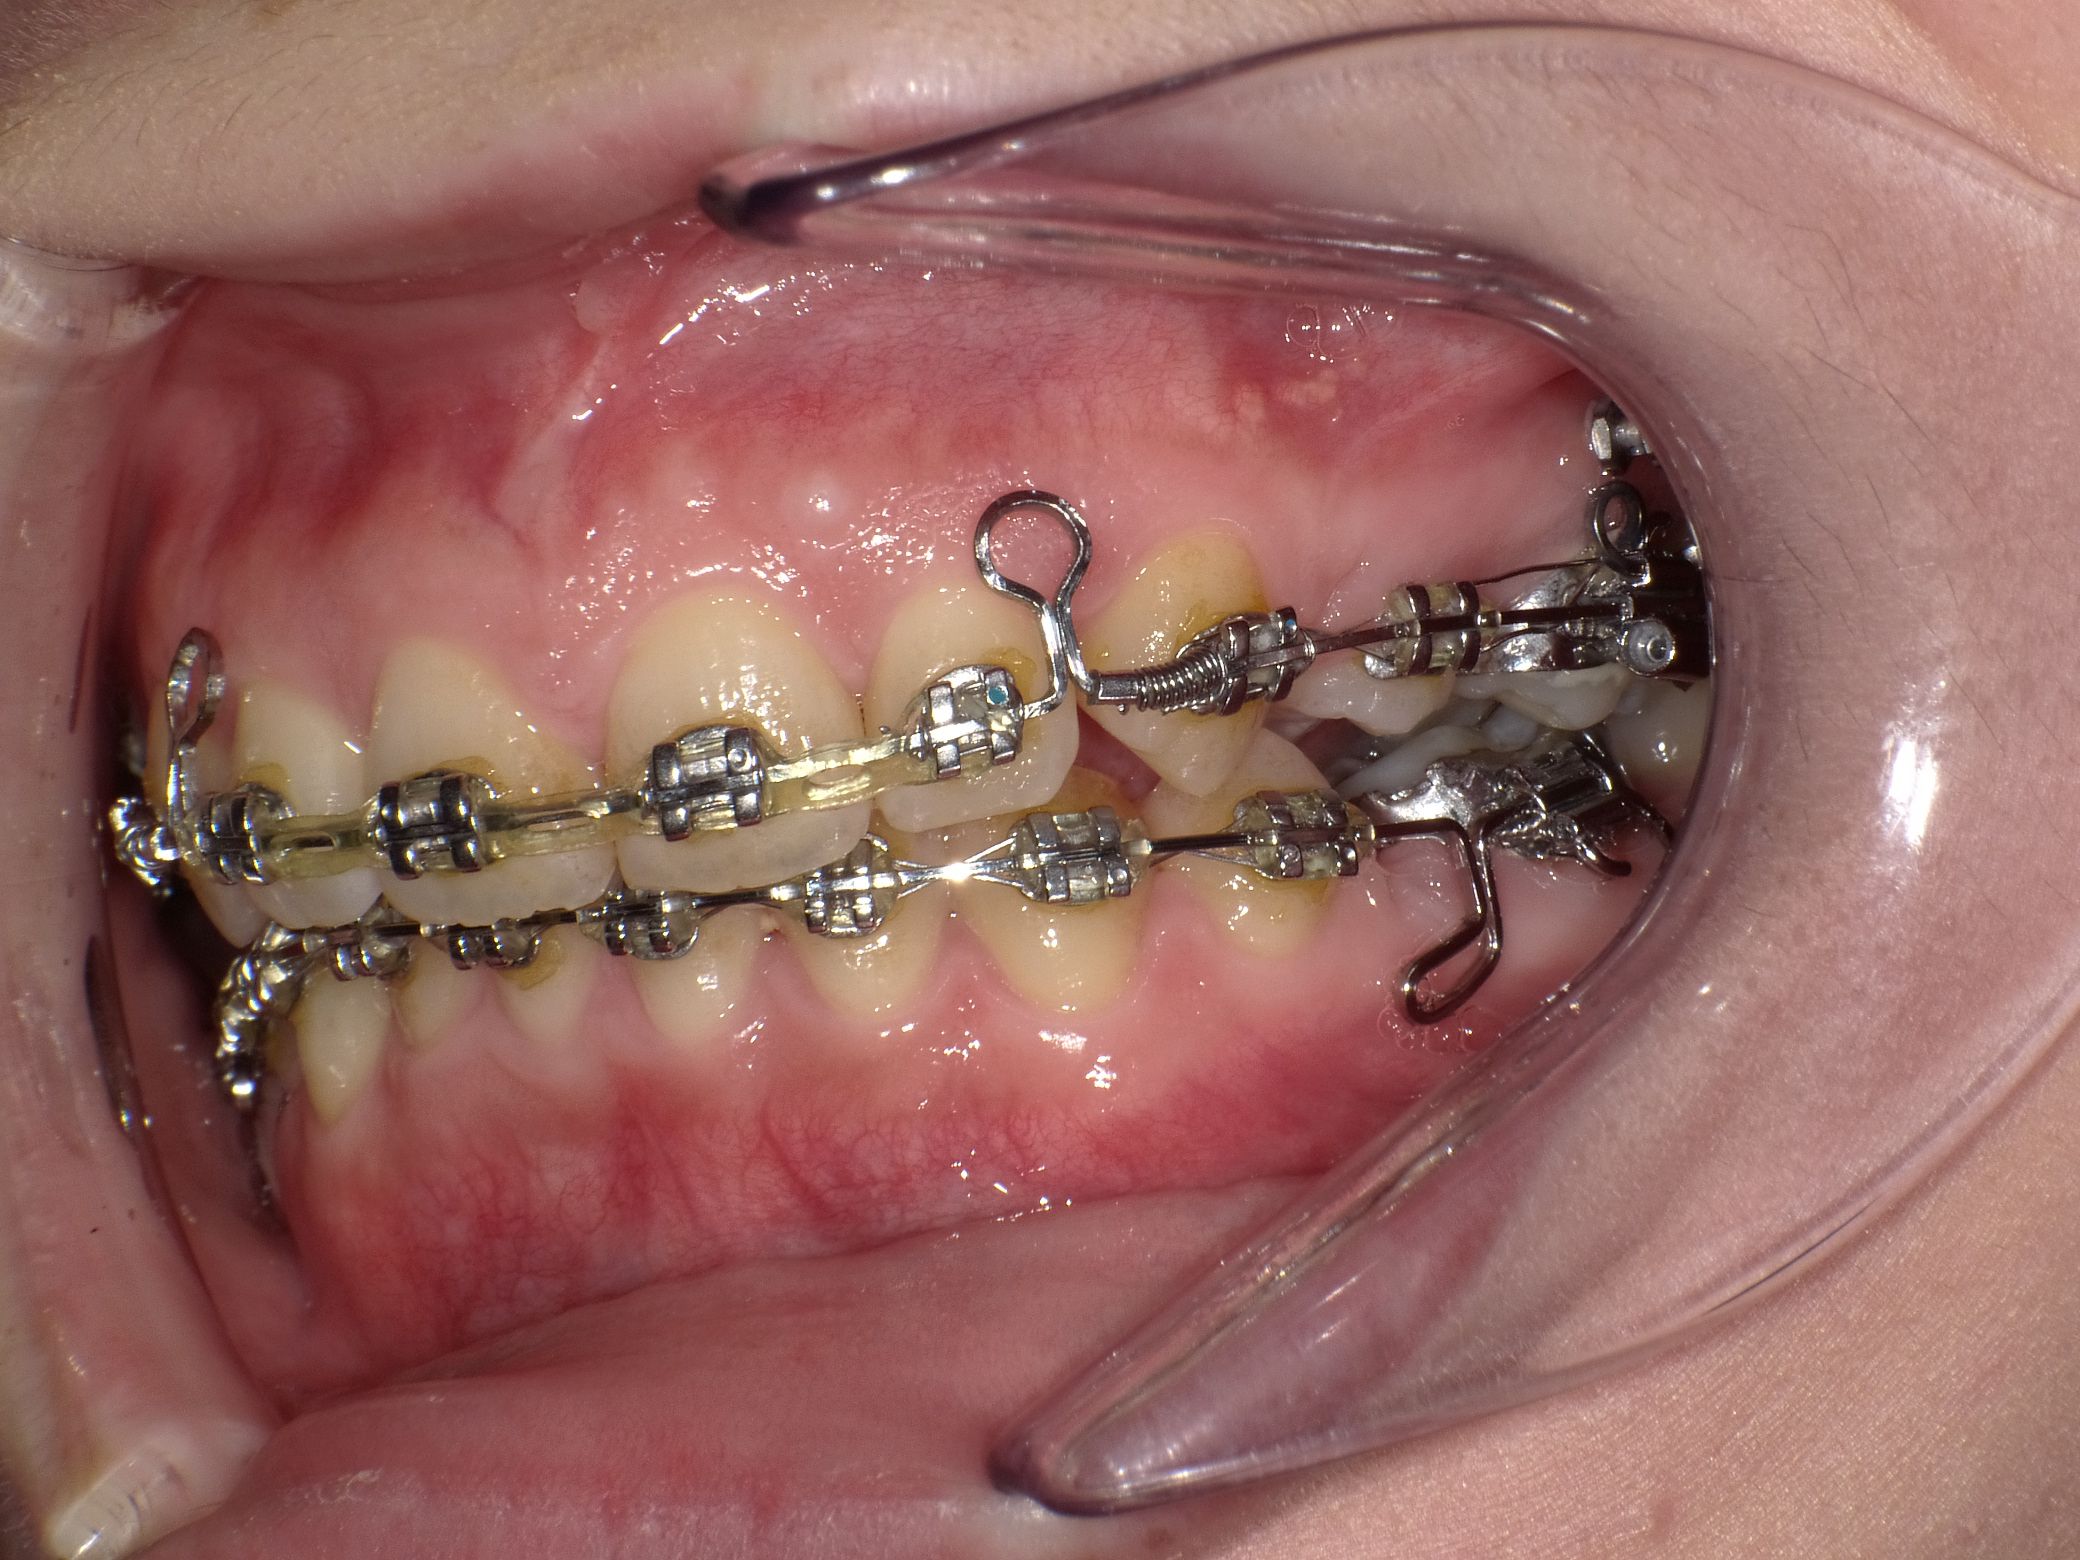

今回は上顎の前歯にゴムをかけてもらいました!

わかりづらいですが、上顎前歯四本にゴムを着けています

前歯が動いて隙間ができないように、ゴムで牽引してくれているのだと思います

実際つけてから前歯の間が以前ほど広がっていないように感じます。

抜歯したところもだいぶ隙間が無くなってきました!歯磨きをするときに特に狭まってきたことを実感しますね

側面が前より磨きにくくなったかな?と、あともう少し狭まったらフロス通したほうがいいかもしれないなと思っています

下顎もちょっとですが動いてますね!停滞期を徐々に脱してきているのかなー?と感じますが、ぬか喜びではないことを祈ります!